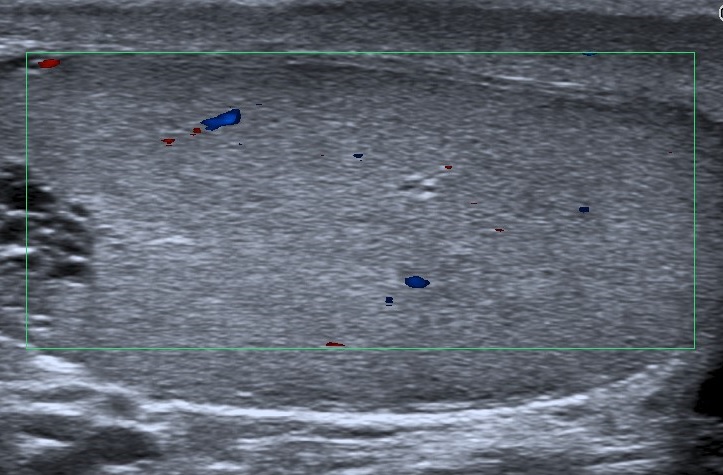

• Se realiza estudio con sonda lineal de alta frecuencia. Se explora el escroto y ambos testículos (figura 1), que presentan tamaño, morfología y ecoestructura normal, así como correcto flujo Doppler (figura 2). A nivel del teste izquierdo, se observa una colección de pequeñas imágenes anecoicas en el mediastino testicular, pseudotubulares. Además, una imagen anecoica, redondeada, quística, a nivel de la cabeza del epidídimo (figura 3).

• Se solicita ecografía testicular reglada que es informada como ectasia tubular de la rete testis en probable relación con antecedente de vasectomía y en la que se visualiza quiste de epidídimo izquierdo de 15 x 8 mm e hidrocele grado I, sin varicocele asociado.